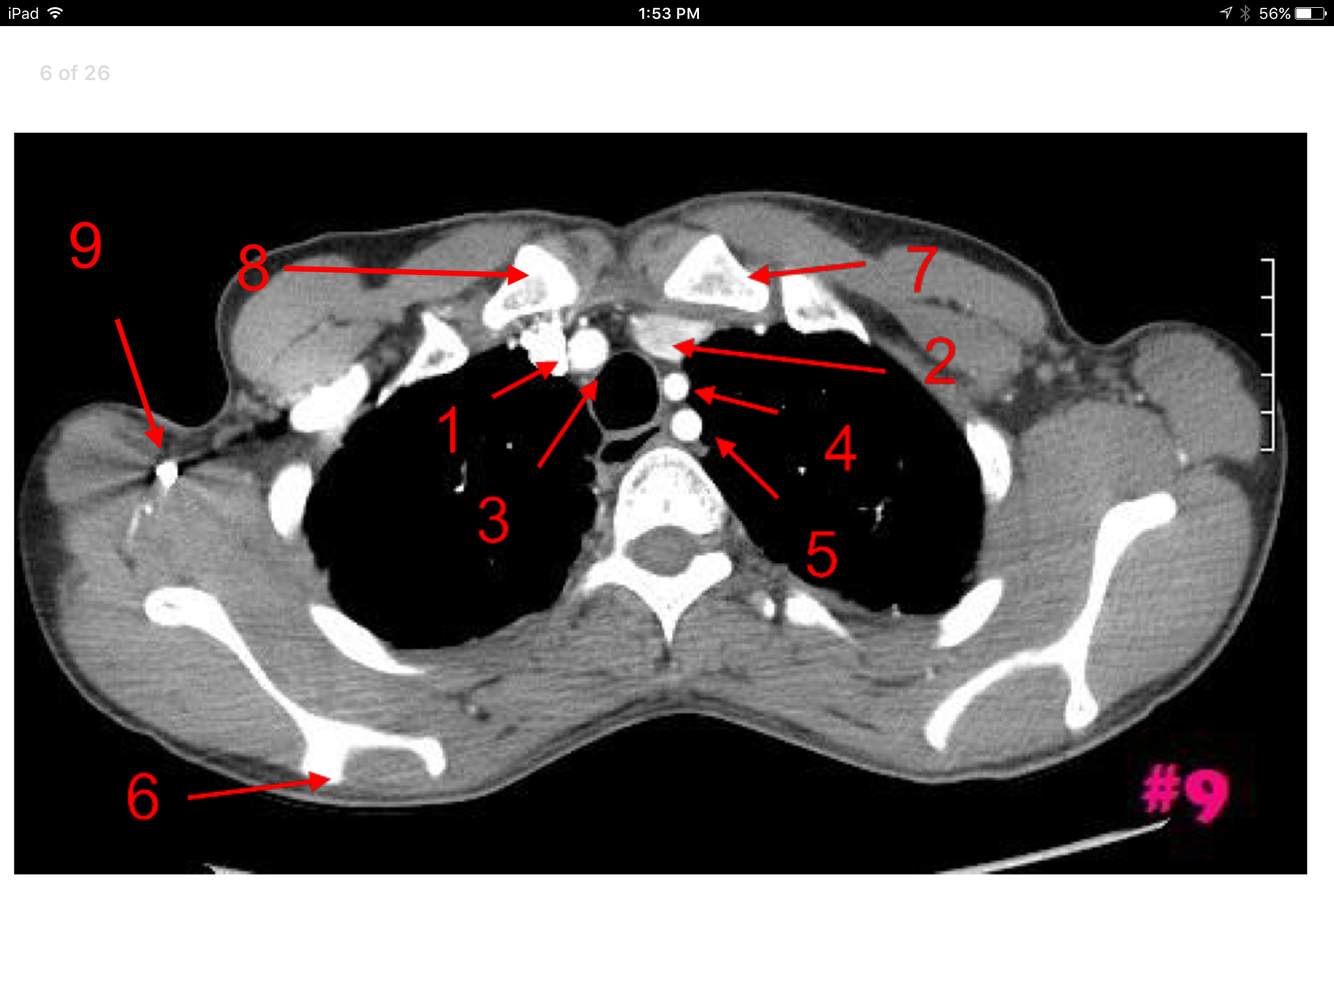

Rt brachiocephalic vein

Lt brachiocephalic vein

Brachiocephalic artery

Lt common carotid artery

Manubrium of the sternum

Lt subclavian artery

Esophagus

Rt axillary vein

Rt subclavian vein

Lt internal jugular vein

Lt subclavian vein